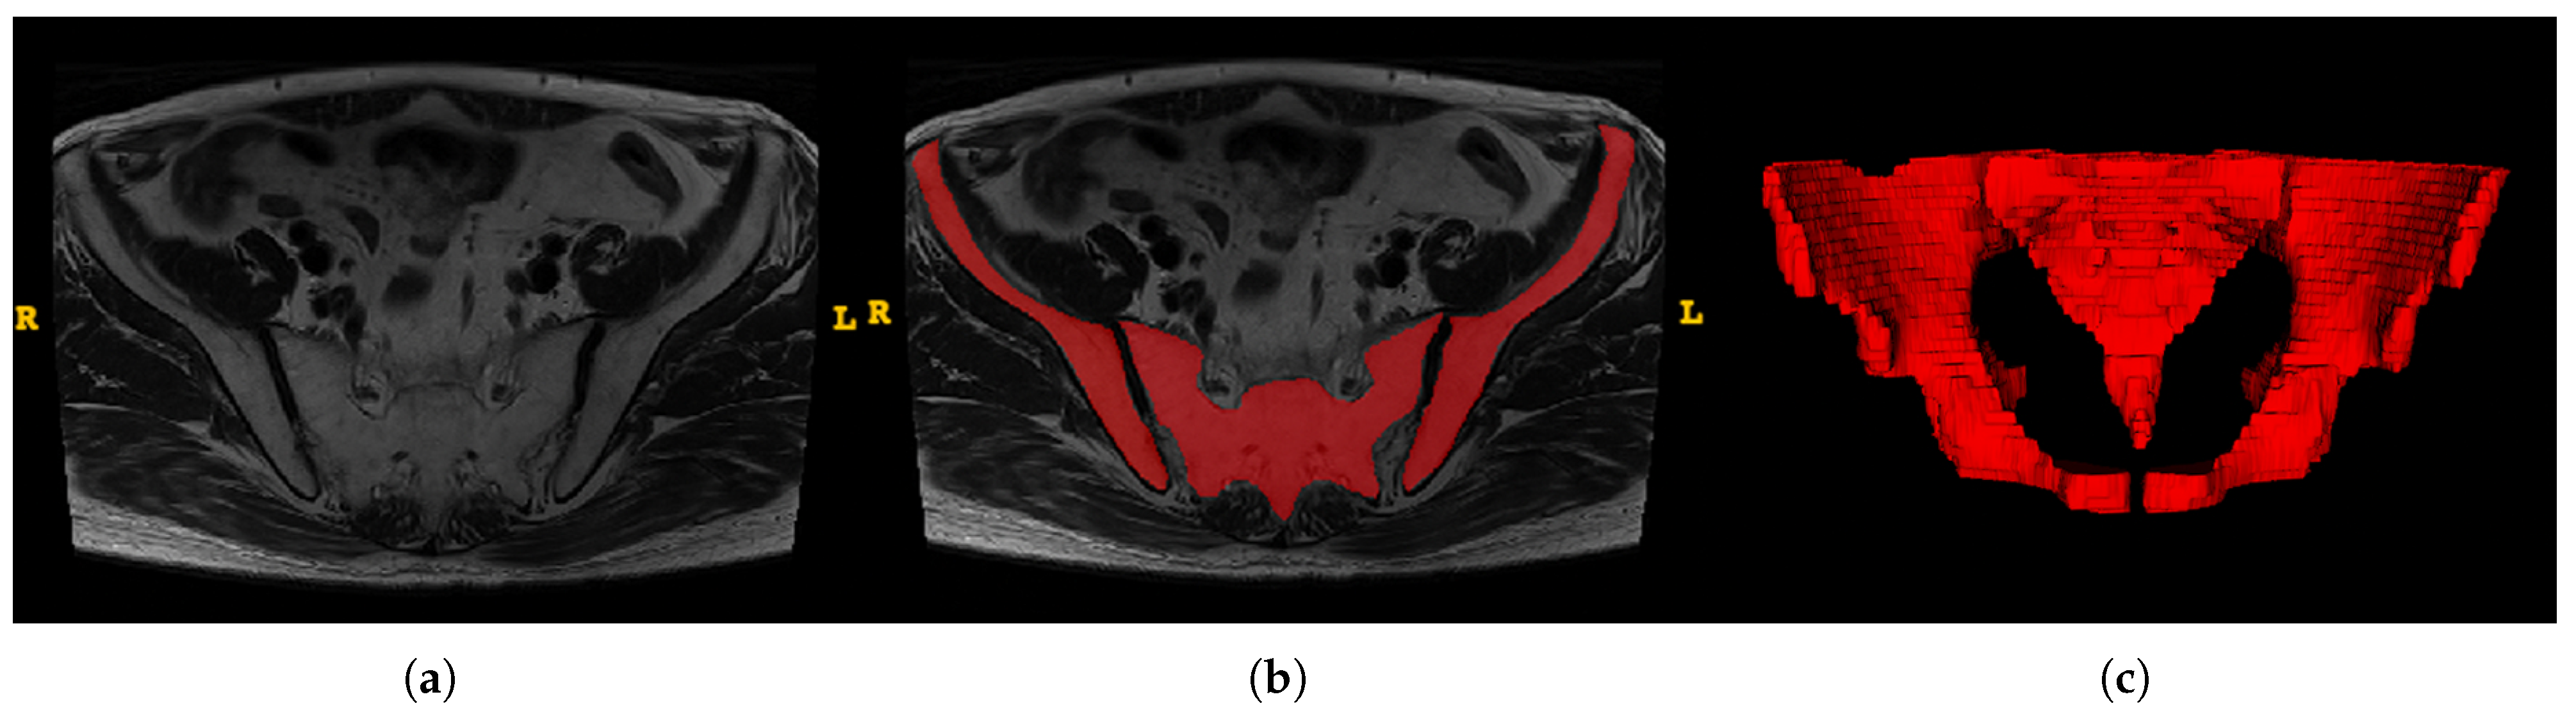

2.2. Image Preprocessing